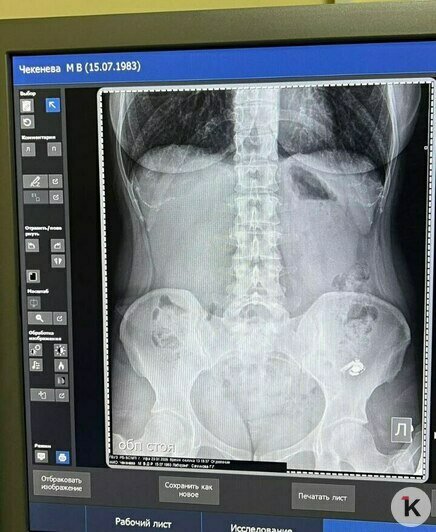

Мария очень испугалась: было непонятно, как поведёт себя внутри организма электронный прибор. Но в травмпункте девушке сделали снимок и обнаружили наушник в желудке. Ей объяснили, что пока ничего страшного не происходит — главное, что он нигде не застрял и не перекрывает дыхательные пути. И порекомендовали подождать, пока гаджет не выйдет естественным путём.

На первом снимке наушник левее: в кадр кроме него случайно попало украшение на теле. Фото: Мария